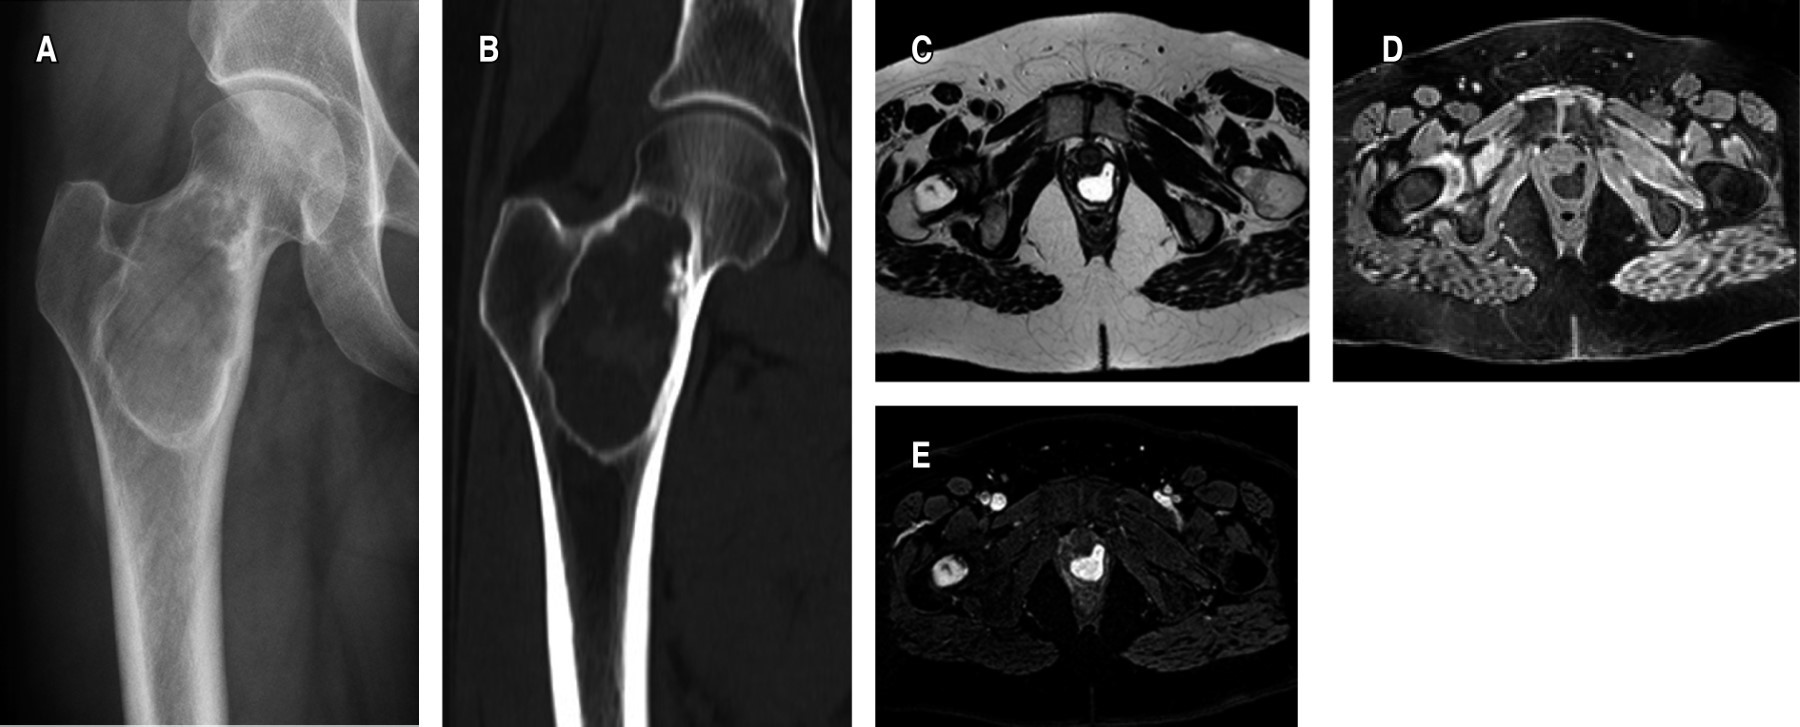

Figure 1